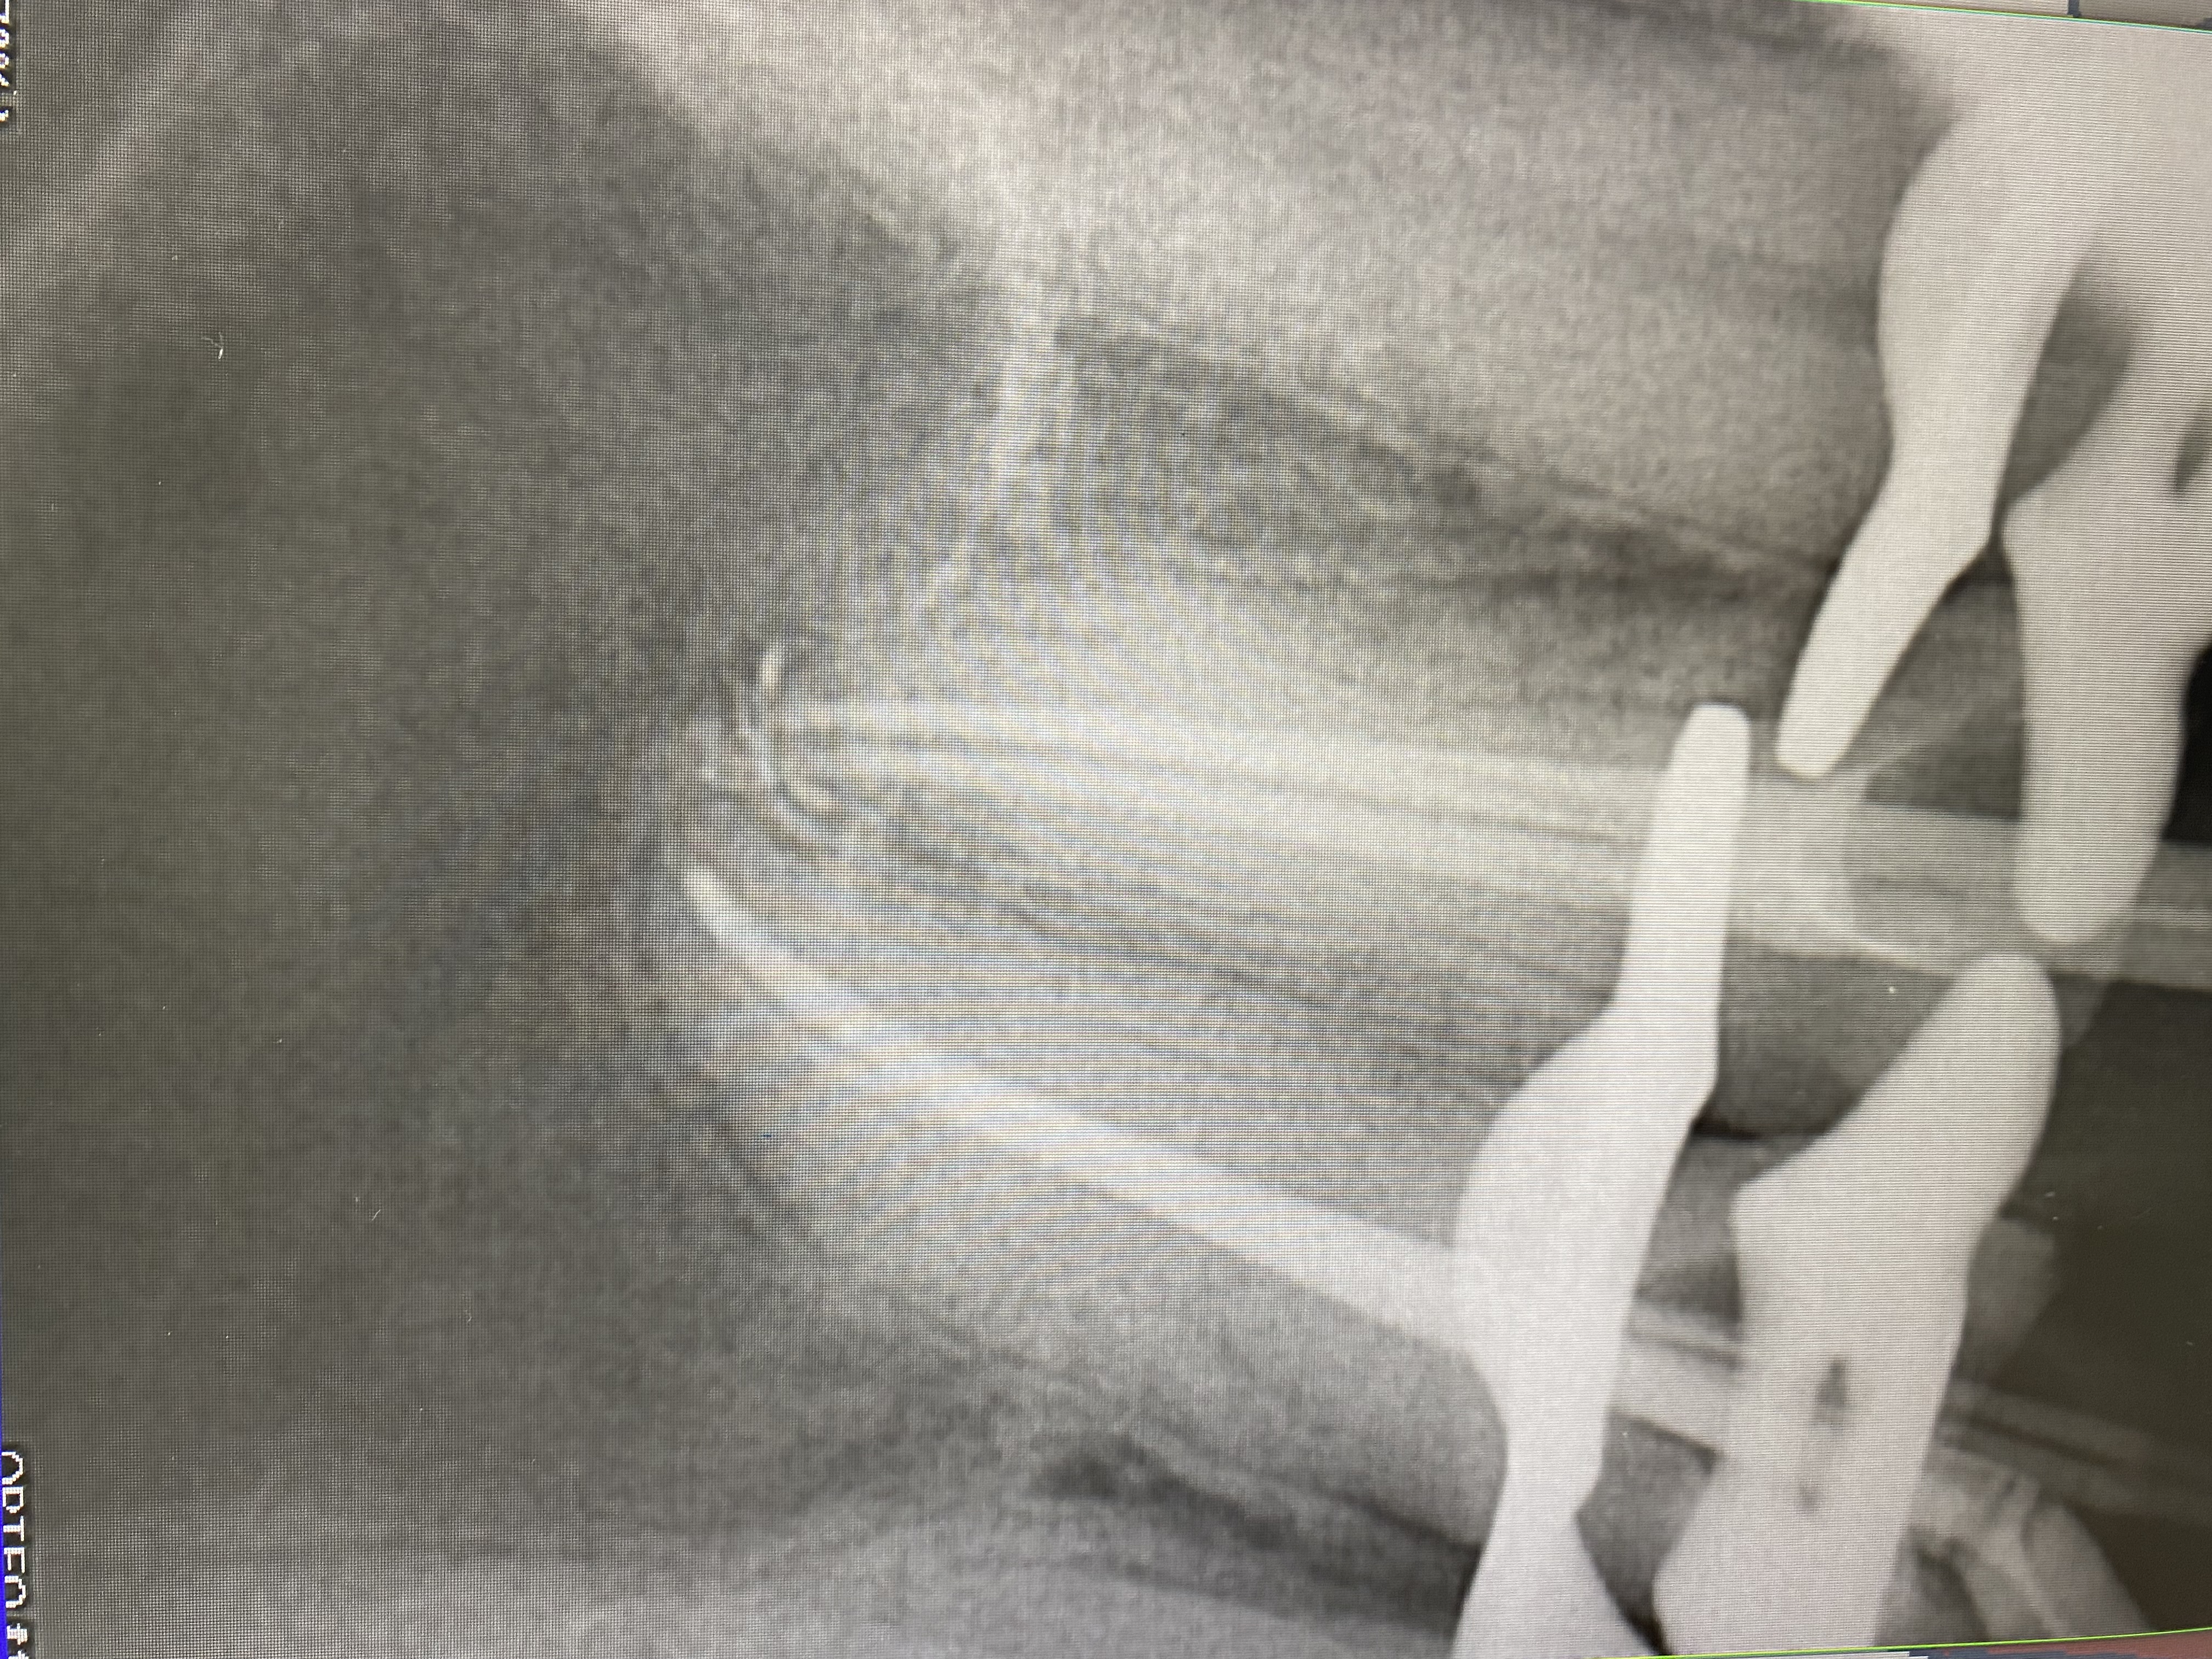

- Владение современными методиками пломбирования корневых каналов, обработки и распломбировки многокорневых зубов любой степени сложности

- 2019г.курс "Повторное эндодонтическое лечение. Консервативные и хирургические методы"

- 2015г.посещение 11-ого международного семинара VDW. Medical consulting group "Эндодонтические аспекты в эндодонтии".

- 2014г.посещение 10-ого Международного эндодонтического семинара VDW.

- 2014г.Перелечивание ортоградная ревизия). клинические решения и техника".

- 2014г.обучение в Medical consulting group "Сложная эндодонтия: трещины, переломы, открытый апекс. Предотвращение, лечение."